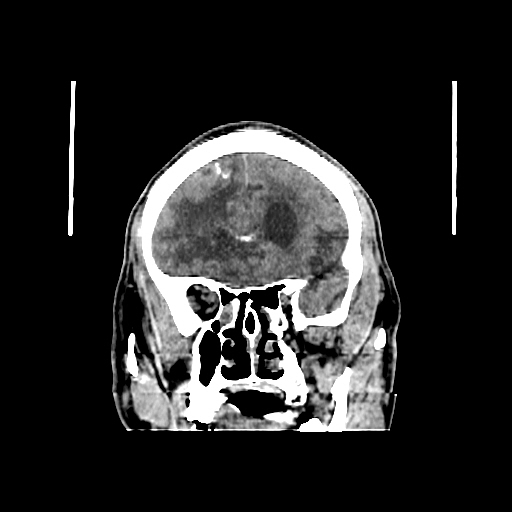

A 60 years old man with seizure since 12 years

Plan CT scan was done on 22 march 2016